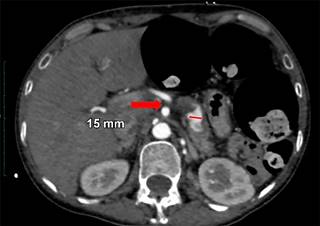

Mujer de 44 años quien 6 meses previos a su ingreso refiere disminución progresiva de la clase funcional debido a un soplo aórtico, por lo que se realizó cambio valvular con la necesidad de ser sometida a circulación extracorpórea y uso de vasopresores. Durante los primeros 10 días postquirúrgicos se diagnostica obstrucción intestinal, por lo que se realiza TC con hallazgo incidental de arteria esplénica (Figura 1) con dilatación aneurismática de hasta 12 mm, en un nuevo estudio de TC a las 24 horas (Figura 2) con ligero aumento del diámetro de aneurisma esplénico hasta 15 mm, pasadas 96 horas solicita nueva TC (Figura 3) y se evidencia mejor definición de la dilatación aneurismática de la arteria esplénica con diámetro actual de 15 mm (previamente de 12 mm). Con los hallazgos tomográficos previamente descritos, se pudo observar la evolución del proceso de dilatación aneurismática con ruptura contenida por el parénquima pancreático, la paciente cursó con un cuadro de obstrucción intestinal con desimpactación endoscópica y dolor abdominal, por lo que seguramente se enmascaró el cuadro clínico.

En nuestro caso, la ruptura de la arteria esplénica en la cual la hemorragia es contenida por el parénquima pancreático logrando sellar el defecto sin presentar pancreatitis y sólo dejando atrás una hipodensidad en el parénquima pancreático subyacente, es extremadamente rara.